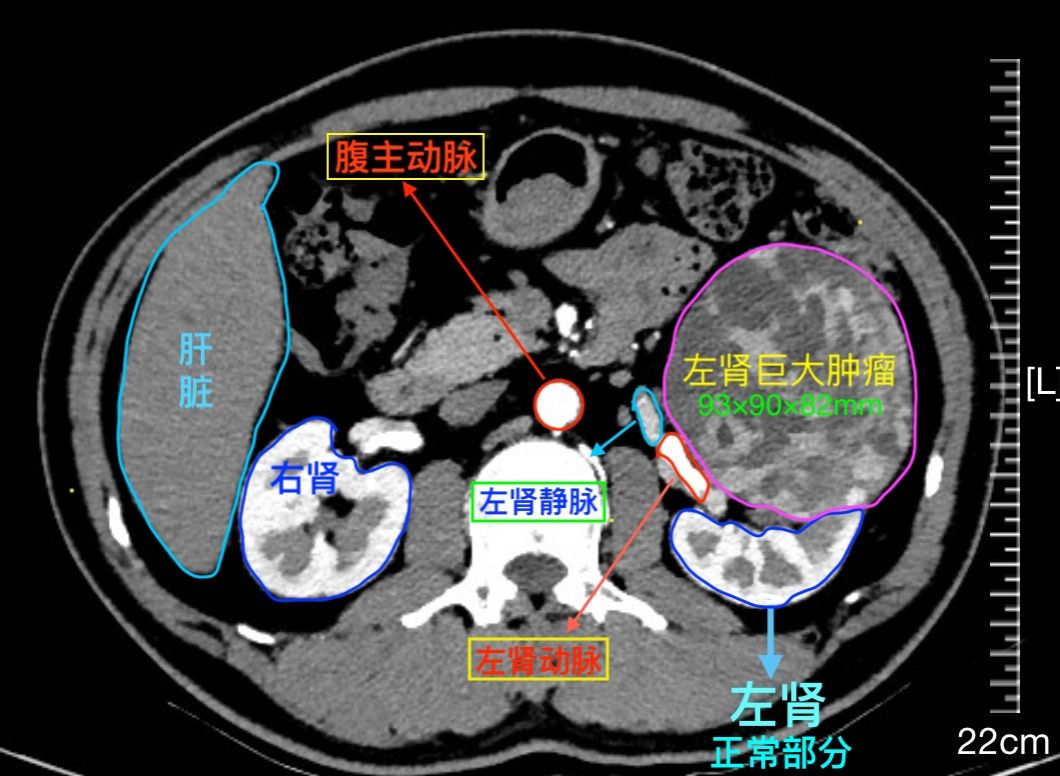

卡在血管网深处的肿瘤!看医生这样操控机器人实施“毫米级”剥离

“肿瘤”两字本来就让人闻之色变,如果它还卡在身体最重要的动静脉深处,紧贴着周围密布的重要血管、神经、器官组织,这可如何是好?近日,南方医科大学第三附属医院泌尿外科团队操控新一代手术机器人,通过一个隐藏于肚脐的3厘米小孔,成功完成了一场精准的微创手术,既完整切除了肿瘤,又保护了所有重要功能。这是该院泌尿肾病医学中心成立后成功拿下的一场“漂亮仗”。据悉,为了更好地服务前列腺癌根治、腹膜后肿瘤切除、复...

来源:第三附属医院

以为只是腰痛,结果腹中藏着20厘米肿瘤!

腹痛腰酸持续半年,40岁的广西刘女士(化名)一直以为是劳累所致。直到症状加剧,在当地医院检查后,结果令人震惊:她的腹腔深处,埋藏着一个直径约20厘米的巨大肿瘤。因肿瘤位置特殊、与重要血管神经纠缠紧密,手术风险极高,求生之路一度陷入僵局。几经辗转,刘女士一家来到广州,求助于南方医科大学第三附属医院(南医三院)。接诊的骨肿瘤科李浩淼主任团队经过详细检查发现,这个位于腹膜后的巨大肿瘤,向上延伸到肝肾间隙...